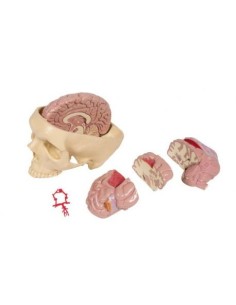

Scopri il Mondo dell’Anatomia con Modelli anatomici di Precisione

Dal cranio in 22 parti con incastri magnetici ai modelli di colonna vertebrale, da quelli di articolazioni a quelli di cuore, ogni pezzo della nostra collezione è progettato per un’immersione totale nello studio dell’anatomia umana. I nostri modelli, realizzati tramite scansioni di ossa vere, garantiscono un’esperienza tattile autentica e una fedeltà di peso quasi identica agli originali.

Essenziali per studenti e professionisti, i nostri modelli anatomici sono strumenti didattici che permettono di osservare le strutture anatomiche con precisione, eliminando la necessità di dissezioni o studi invasivi. Sono inoltre utili per spiegare ai pazienti le patologie, rendendo la comunicazione più efficace e risparmiando tempo prezioso.